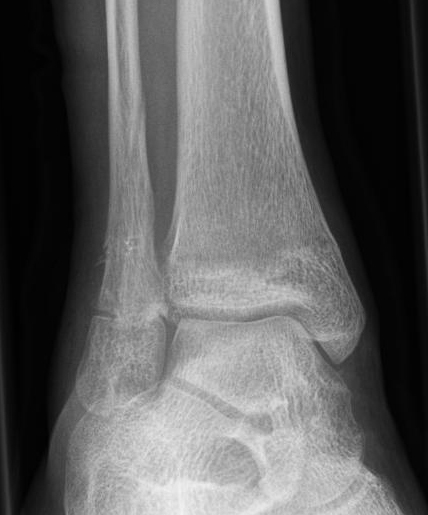

Fugengelenkfrakturen treten typischerweise vor dem 10. Lebensjahr auf, in einer Phase, in welcher die Wachstumsfugen noch weit offen sind. Dieser Frakturtyp betrifft fast ausschließlich den medialen Malleolus. Laterale Frakturen sind extrem selten, teilweise kommt es zu lateralen Bandverletzungen oder Fugenschaftfrakturen der distalen Fibula. Die Frakturlinie verläuft in einer Verlängerungslinie von der medialen Taluskante nach proximal. Häufig stellen sich Verletzungen des Innenknöchels im Röntgenbild schlechter dar, insbesondere wenn die Aufnahmen verdreht sind oder die Ebene der Fraktur bei geringer Dislokation verkippt zur Röntgenebene liegt. Besteht klinisch der geringste Hinweis auf eine Verletzung des Innenknöchels, muss aufgrund der Tragweite der Verletzung durch entsprechende Aufnahmen gegebenenfalls auch Schnittbildverfahren die Verletzung sicher diagnostiziert oder ausgeschlossen werden (Abb. 15).